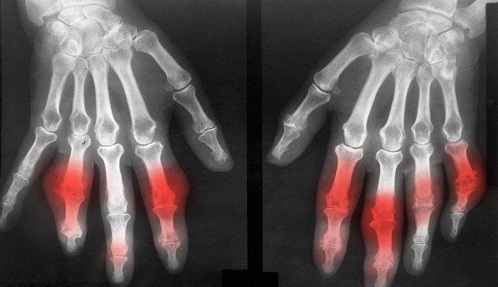

痛风是由体内一种叫做“嘌呤”的物质代谢紊乱,体内尿酸产生多或肾脏排泄尿酸减少,从而引起血中尿酸升高,形成尿酸血症以及频繁发作的痛风性急性关节炎,痛风石沉积,痛风性慢性关节炎和关节畸形及肾脏病变等为特征。在我国,由于缺乏对痛风危害性的足够认识,很多人都会忽视前期的治疗,从而错过了的治疗时机!》》》不懂?有疑问?——点击咨询在线医生

值得警惕的是,痛风并不是单一的疾病,而是一种综合症,单纯的吃药可以清除体内的尿酸,但是不能清除关节处的尿酸盐沉积,这也是痛风之所以频繁发作的原因所在。